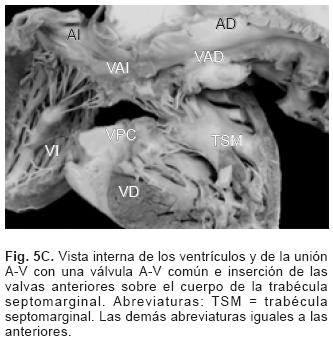

De los sesenta y cinco corazones con válvula común en veinticinco se determinaron los tipos de la clasificación de Rastelli que fueron los siguientes: en once (44%) las valvas anterosuperiores derecha e izquierda se insertaron a través de sus cuerdas tendinosas sobre la cresta del tabique ventricular y la CIV se ubicó en los espacios intercordales (tipo A de Rastelli) (Figs. 1A y 5A). En un espécimen las valvas anterosu–periores izquierda (valva puente) y derecha se insertaron sobre la cara derecha del tabique ventricular por debajo de su cresta (Fig. 5B) y en otro dicha inserción se hizo en la parte superior del cuerpo de la trabécula septomarginal (Fig. 5C). En ocho corazones (32%) la inserción de esas valvas se estableció en un músculo papilar situado en la unión del tabique ventricular con la pared libre del ventrículo derecho y la valva anterosuperior izquierda pasó como puente por encima de la CIV (tipo B de Rastelli) (Figs. 1B y 5D) y en seis corazones (24%) la inserción de las valvas anterosuperior izquierda (valva puente) y derecha se insertaron en un músculo papilar de la pared libre del ventrículo derecho y esta valva se ubicó por encima de la CIV (tipo C de Rastelli) (Figs. 1C y 5E). En los cuarenta corazones restantes no fue posible determinar los tipos de Rastelli debido a que treinta y tres de ellos presentaron doble entrada ventricular (Fig. 6A) dos tuvieron modificaciones anatómicas generadas por la cirugía y cinco por presentar mutilaciones realizadas durante la necropsia. Los cinco especímenes con dos válvulas separadas tuvieron estructura trifoliada dentro de la unión A–V común (Figs. 3B y 6B); la válvula A–V izquierda mostró una valva lateral y dos septales anterior y posterior unidas a la cresta del tabique ventricular, lo que obliteró la CIV (Fig. 6C). La válvula A–V derecha mostró una valva septal displásica, una anterior y una posterior (Figs. 3B y 6B).